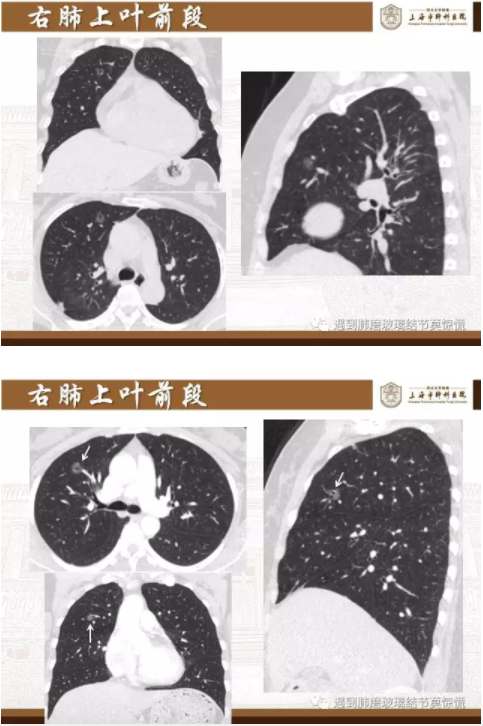

下面就我们的病例分析一下怎么进行肺段切除。

MIA= 微浸润腺癌   IA= 浸润性腺癌   AIS= 原位腺癌   AAH= 不典型腺瘤样增生